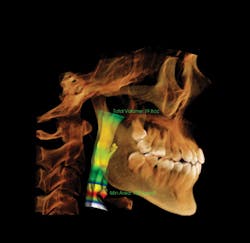

I attend the Texas Dental Association meeting each year and it proved to be an excellent time to meet with vendors. I spoke with almost every company that has a cone beam unit. I kept coming back to Instrumentarium. The OP300 Maxio had the field of view we needed-from a targeted 5 x 5 cm scan to a comprehensive condyle-to-condyle view that includes the airway-and I liked the clean look of the machine. What finally sold me was the rep we worked with, Jimmy. He was a superstar. We've had the unit in our practice for almost a year now and he's taken care of us every step of the way. With training, support, and cost, he's provided excellent service and proven to be extremely knowledgeable.

The OP300 Maxio offers extended fields of view for diagnosis and treatment of the entire maxillofacial region.

13x15 covers the entire maxillofacial region.

Larger fields of view offer broader diagnostic capabilities, including airways.